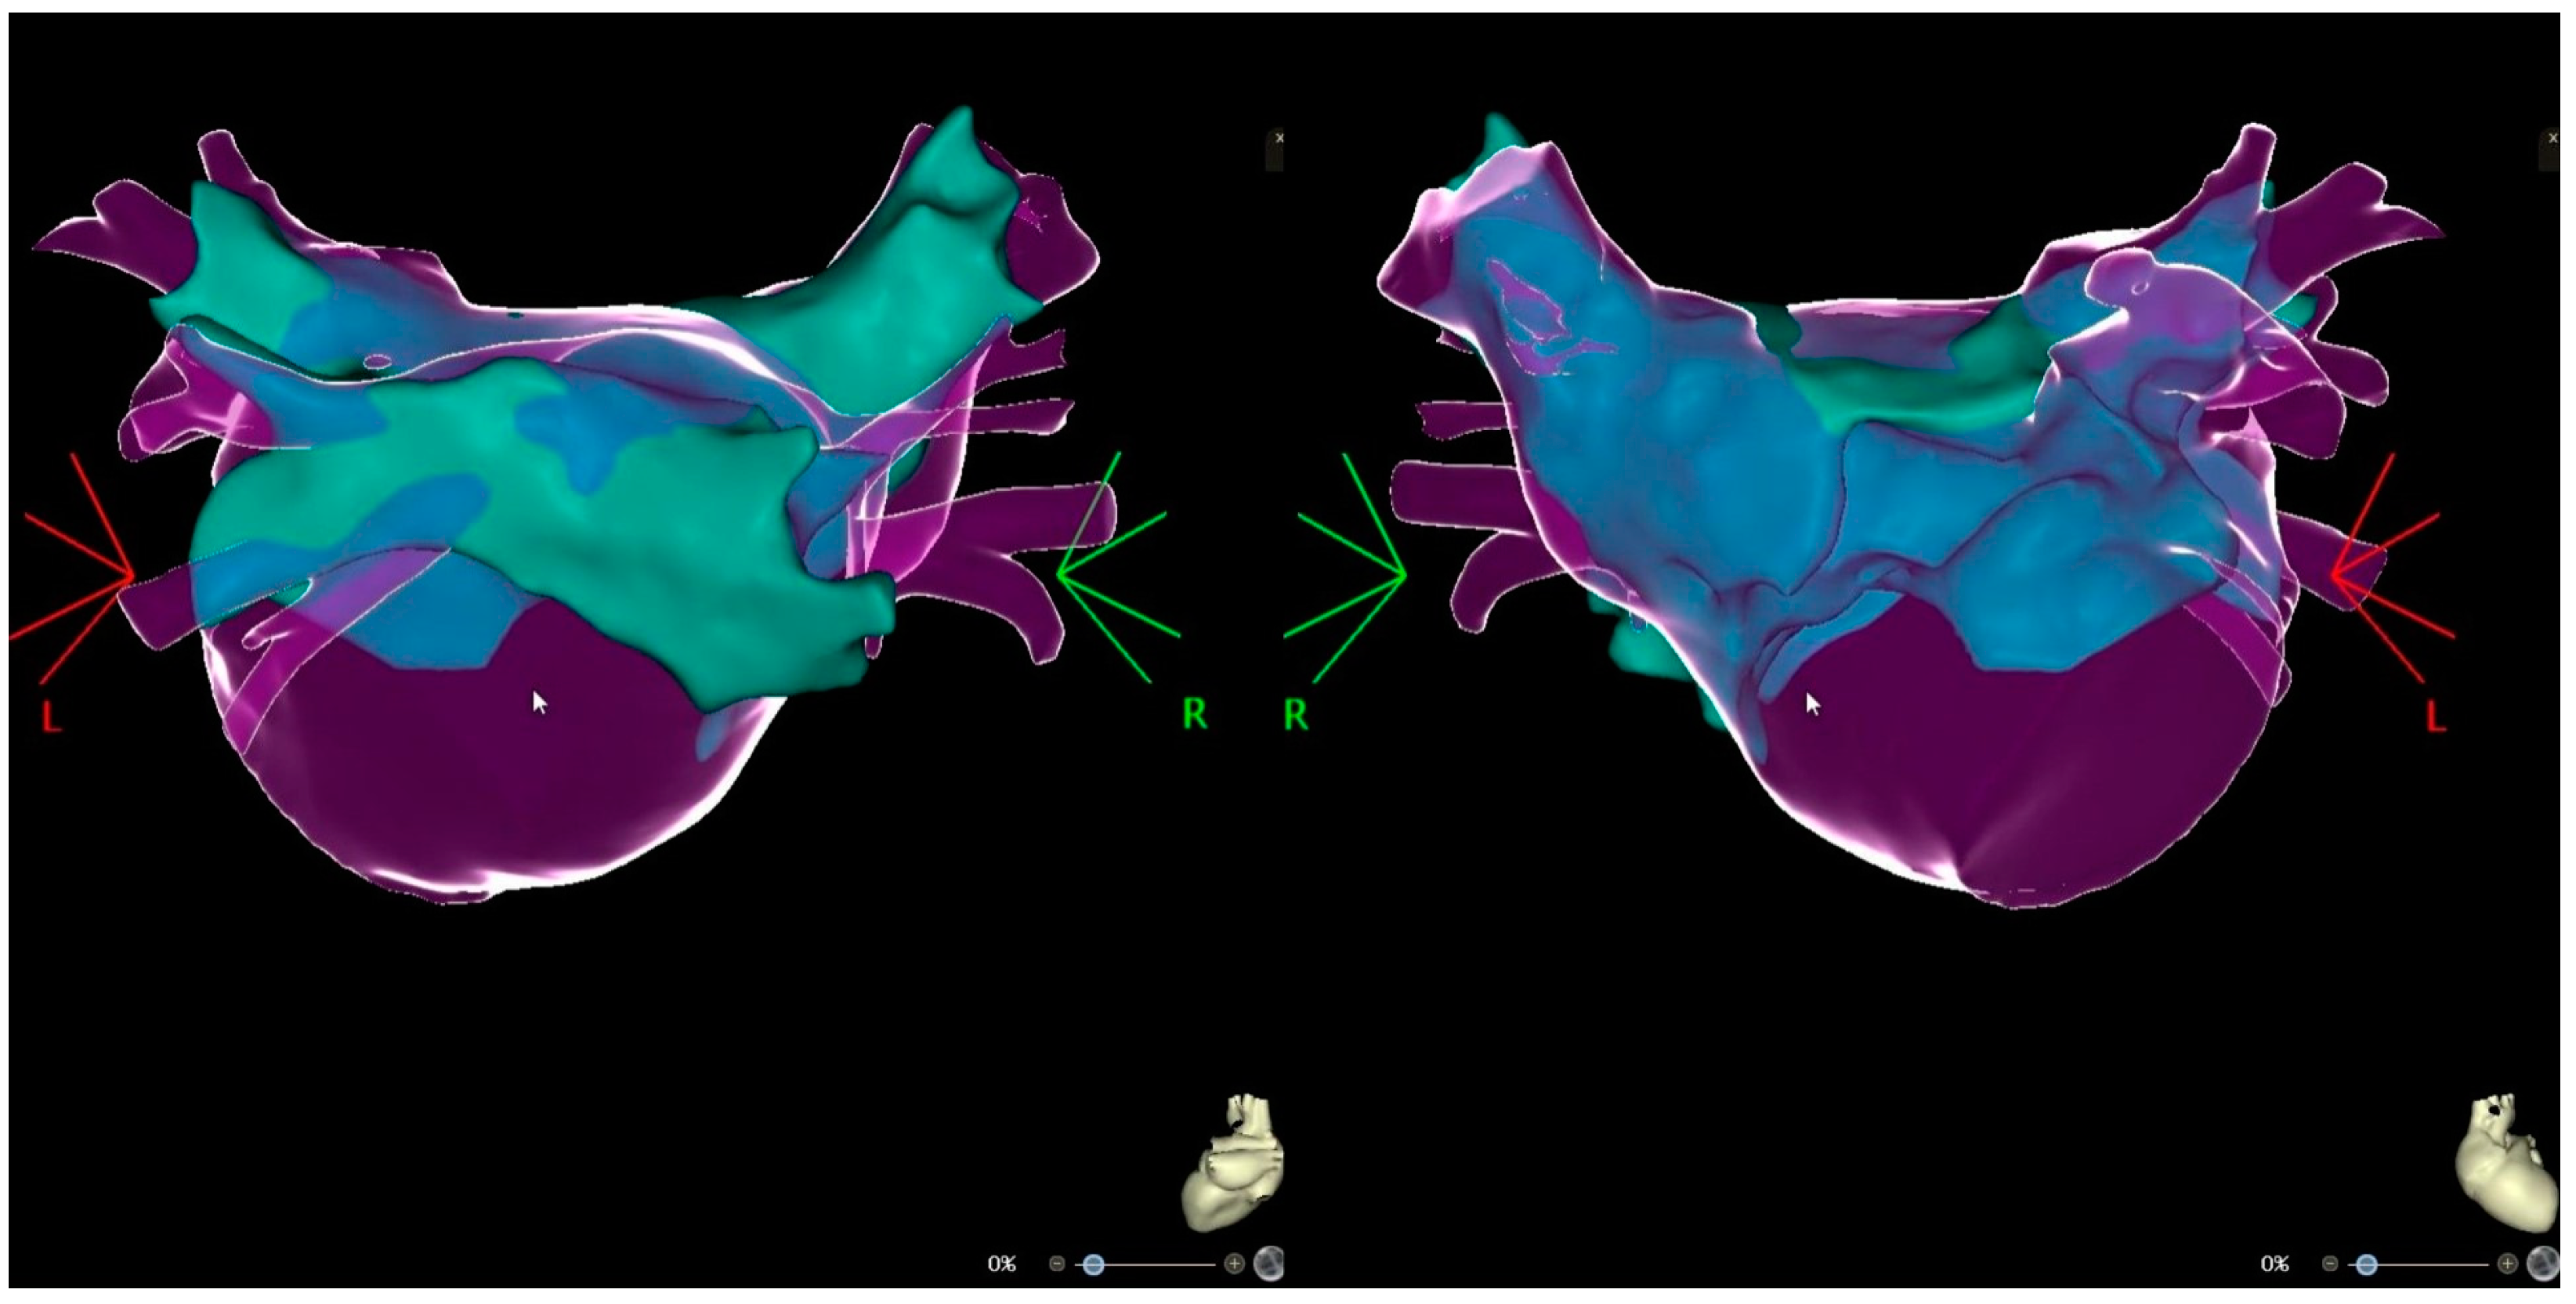

2. Case Presentation